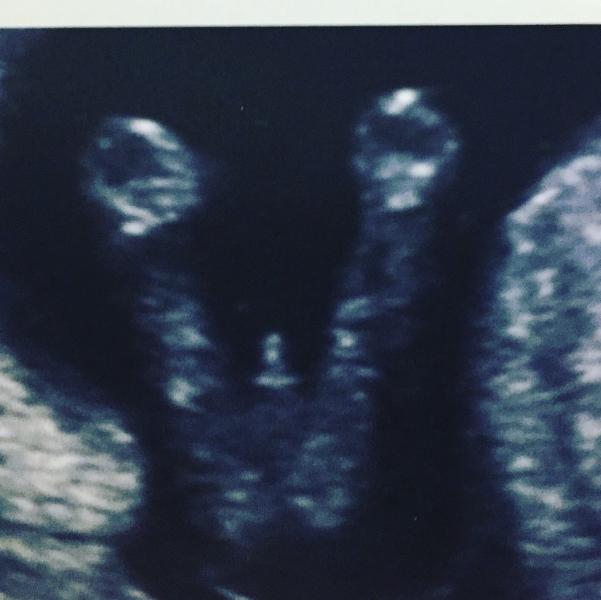

@sregina, там 100% сказали, все чётко понятно, писюн и яйки)) мы на платное ходили, во всех проекциях рассмотрели)

может пуповины так? у девочки так было) тем более срок 16 недель)